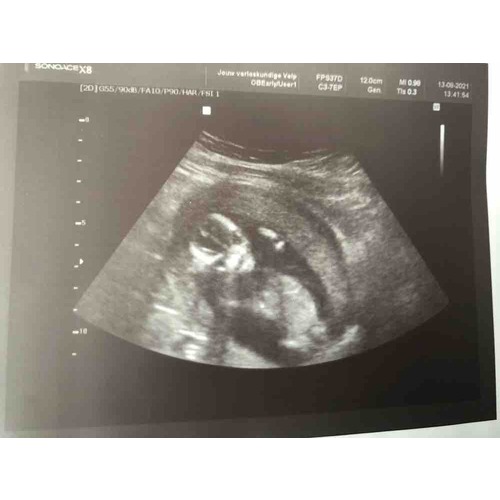

Leuke echo foto heb je trouwens, bijna dezelfde als ik!